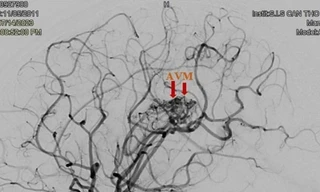

TPO - Cho rằng con học nhiều nên bị đau đầu gia đình không đưa đến bệnh viện thăm khám, hơn 1 tháng sau bé gái 12 tuổi rơi vào tình trạng yếu nửa người bên trái. Tại bệnh viện, bác sĩ xác định trẻ bị đột quỵ do vỡ dị dạng mạch máu não.